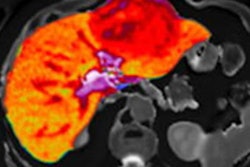

Image analysis software developer Perspectum Diagnostics is expanding development of its artificial intelligence (AI) algorithm to include cardiac and lung imaging.

The company has launched two new studies: Coverscan and Modify. The studies involve aortic and cardiac imaging with MRI and are particularly aimed at better understanding the impact and progression of COVID-19 disease (Coverscan) and diabetes (Modify).

The studies are part of Perspectum's further development of its Atlas metabolic software suite, according to the firm.